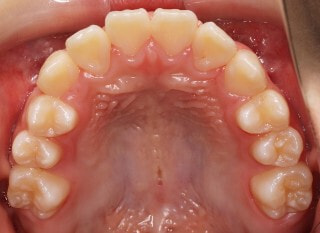

小児期第二段階

開始時